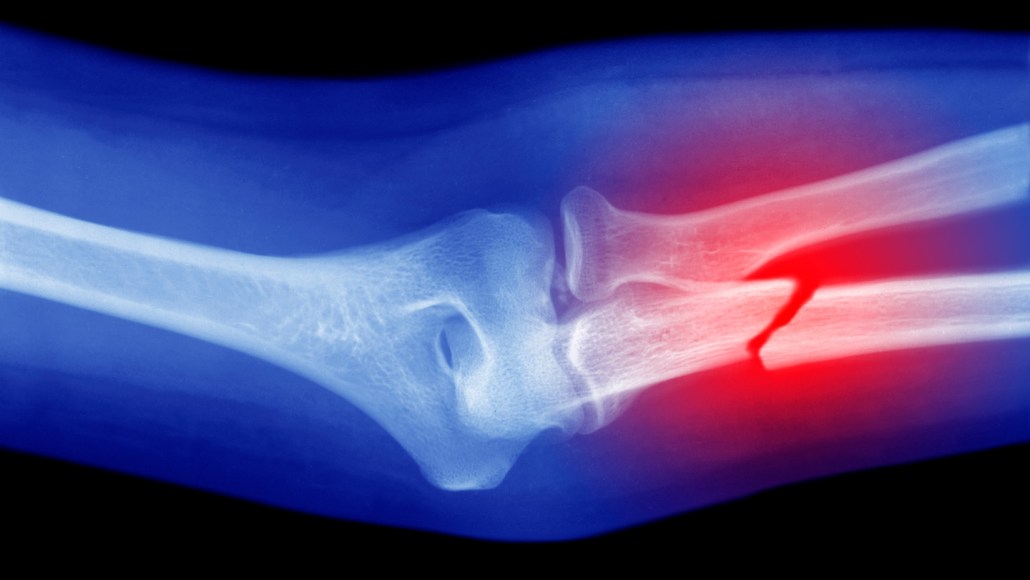

A handheld 3-D printer, prototyped with a modified glue gun, might someday print bone grafts directly onto fractures, complete with antibiotics to ease healing.

Lee and his colleagues tested the glue gun and bioink on femoral bone fractures in rabbits. Comparing results from rabbits receiving the therapy with a control group receiving regular bone cement, the team found that the former group had better healing and regeneration of bone tissue. The animals also showed no signs of infection during the 12 weeks following surgery.